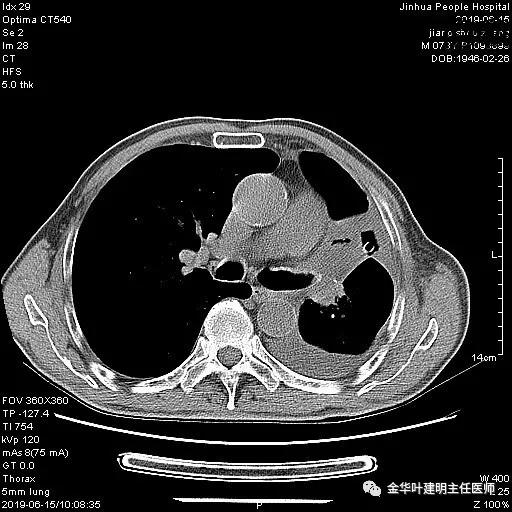

以上是肺窗表现,下面为纵隔窗影像:

6.15上午:24小时胸管引流出血性液250ml;复查胸部CT示: